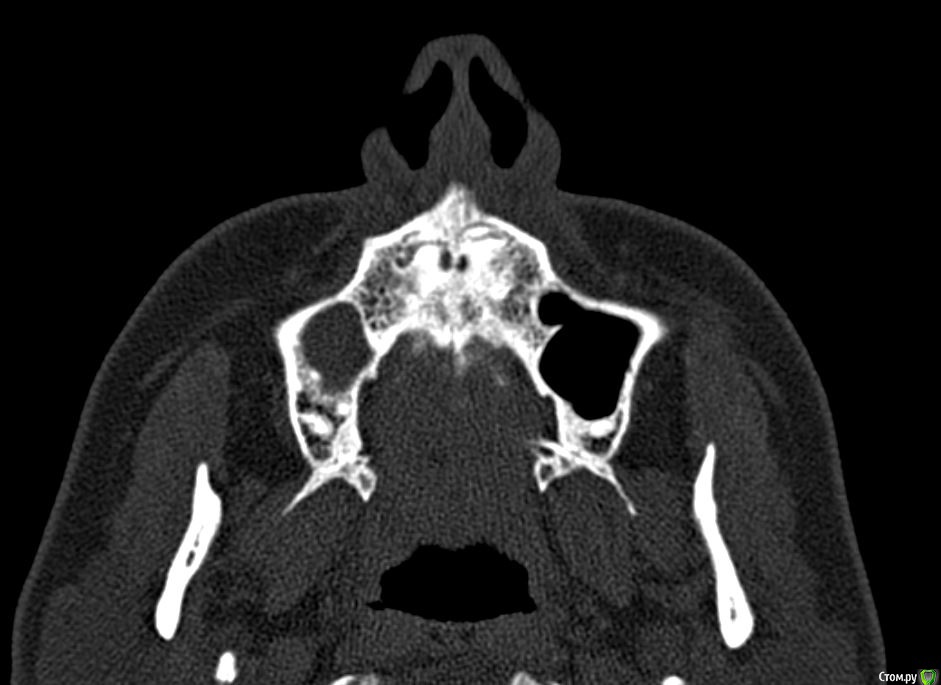

Лисица Опубликовано 26 июля, 2015 Автор Поделиться Опубликовано 26 июля, 2015 (изменено) Вы же не думаете, что Вам назначат а/б терапию по интернету? Я просто не знаю, исходя из каких показателей она назначается. Поэтому осведомилась на всякий случай. Итак, сходила я сегодня на КТ. И по ходу мне сделали что-то не то... Когда я обратилась в клинику, я уточнила, что мне нужно КТ для эндодонтии, чтобы видно было каналы, с достаточным разрешением, чтобы было видно зубы и их корни, входящие в верхнечелюстной синус. Администратор клиники уточнила у врача и сказала, что мне нужно заказывать не КТ верхней челюсти, а КТ пазух. У рентгенолога я также повторила все описанное, рассказала, что при лечении каналов вчера была продырявлена пазуха, уточнила, будут ли видны как следует зубы и их каналы, меня заверили, что "все будет". Причем у врача, судя по описанию на сайте клиники, была ординатура по хирургии в медико-стоматологическом университете, так что он, уж наверное, понимал, что мне нужно. В итоге я получила пленку со снимками формата чуть ли не А3 и диск. На пленке все зубы были просто белыми и коронки видны не целиком. Заключение: в правой верхнечелюстной пазухе уровень жидкости, острый правосторонний гайморит.Думала, может в программе можно будет увеличить разрешение. Но похоже, что нет... или я просто ламер? Зубы просто размытые и белые... Прилагаю сделанные мной скриншоты, как мне кажется, наиболее показательные... Если нужно другие "виды", то скажите какие, или такие снимки вообще ни о чем? Программа просмотра называется Philips DICOM Viewer R3.0-SP03. Аппарат был не местный "на голову", а здоровый, куда заезжаешь в лежачем положении. Изменено 26 июля, 2015 пользователем Лисица Ссылка на комментарий

Лисица Опубликовано 26 июля, 2015 Автор Поделиться Опубликовано 26 июля, 2015 Тьфу ты, Акелла промахнулся. Не та сторона в профиль. Вот парочка проекций с нужной больной стороны. Ссылка на комментарий

Лисица Опубликовано 26 июля, 2015 Автор Поделиться Опубликовано 26 июля, 2015 О, кажись я накопала настройки для более-менее понятного отображения Хоть и не уверена, что это то что нужно. Ссылка на комментарий

St. Опубликовано 27 июля, 2015 Поделиться Опубликовано 27 июля, 2015 Гайморит справа есть, и жидкость тоже. Корни этого зуба действительно заканчиваются в гайморовой.Ничего такого страшного, чтоб однозначно удалять зуб я не вижу. С гайморитом - к лорам на лечение.В зубе я бы ещё раз поменяла лекарство на пару недель, пока гайморит не притихнет, потом постоянно пломбировать. 1 Ссылка на комментарий